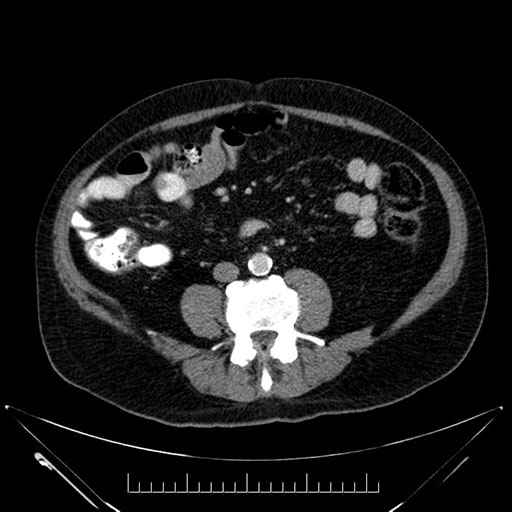

Axial - stented